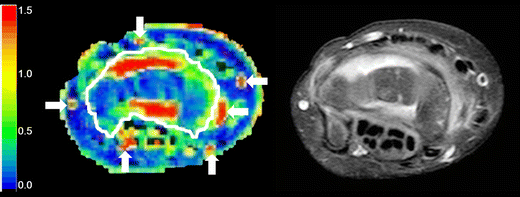

Example of a manually drawn region of interest (white line) on the maximal enhancement map (left) based on axial wrist MRI in a 9-year-old female with clinically active juvenile idiopathic arthritis. The arrows indicate the arteries and vessels, which have not been included in the region of interest. A high spatial resolution T1-weighted image with fat saturation after intravenous contrast administration (right) is added for anatomical reference

While bones of the wrist joint were included in the region of interest, they do not contribute to the final result as the bone does not enhance on dynamic contrast-enhanced MRI and all the results were calculated only on enhancing voxels (types 2 to 7).

Conventional descriptive measures included the median value of maximum enhancement (maximum enhancement of all enhancing voxels within the region of interest with time-intensity-curve shapes 2-7), median maximum initial slope (maximum slope of increase of all enhancing voxels within the region of interest with time-intensity-curve shapes 2-7), median initial area under the curve (area under the enhancement curve between start of injection and 90 s after injection) and the enhancing volume (total volume in millimeters of all enhancing voxels within the region of interest with time-intensity-curve shapes 2-7).